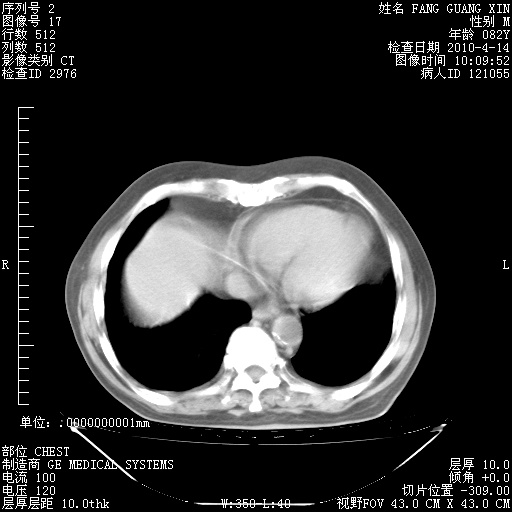

4月14日肺部CT

肺部CT平扫未见异常。